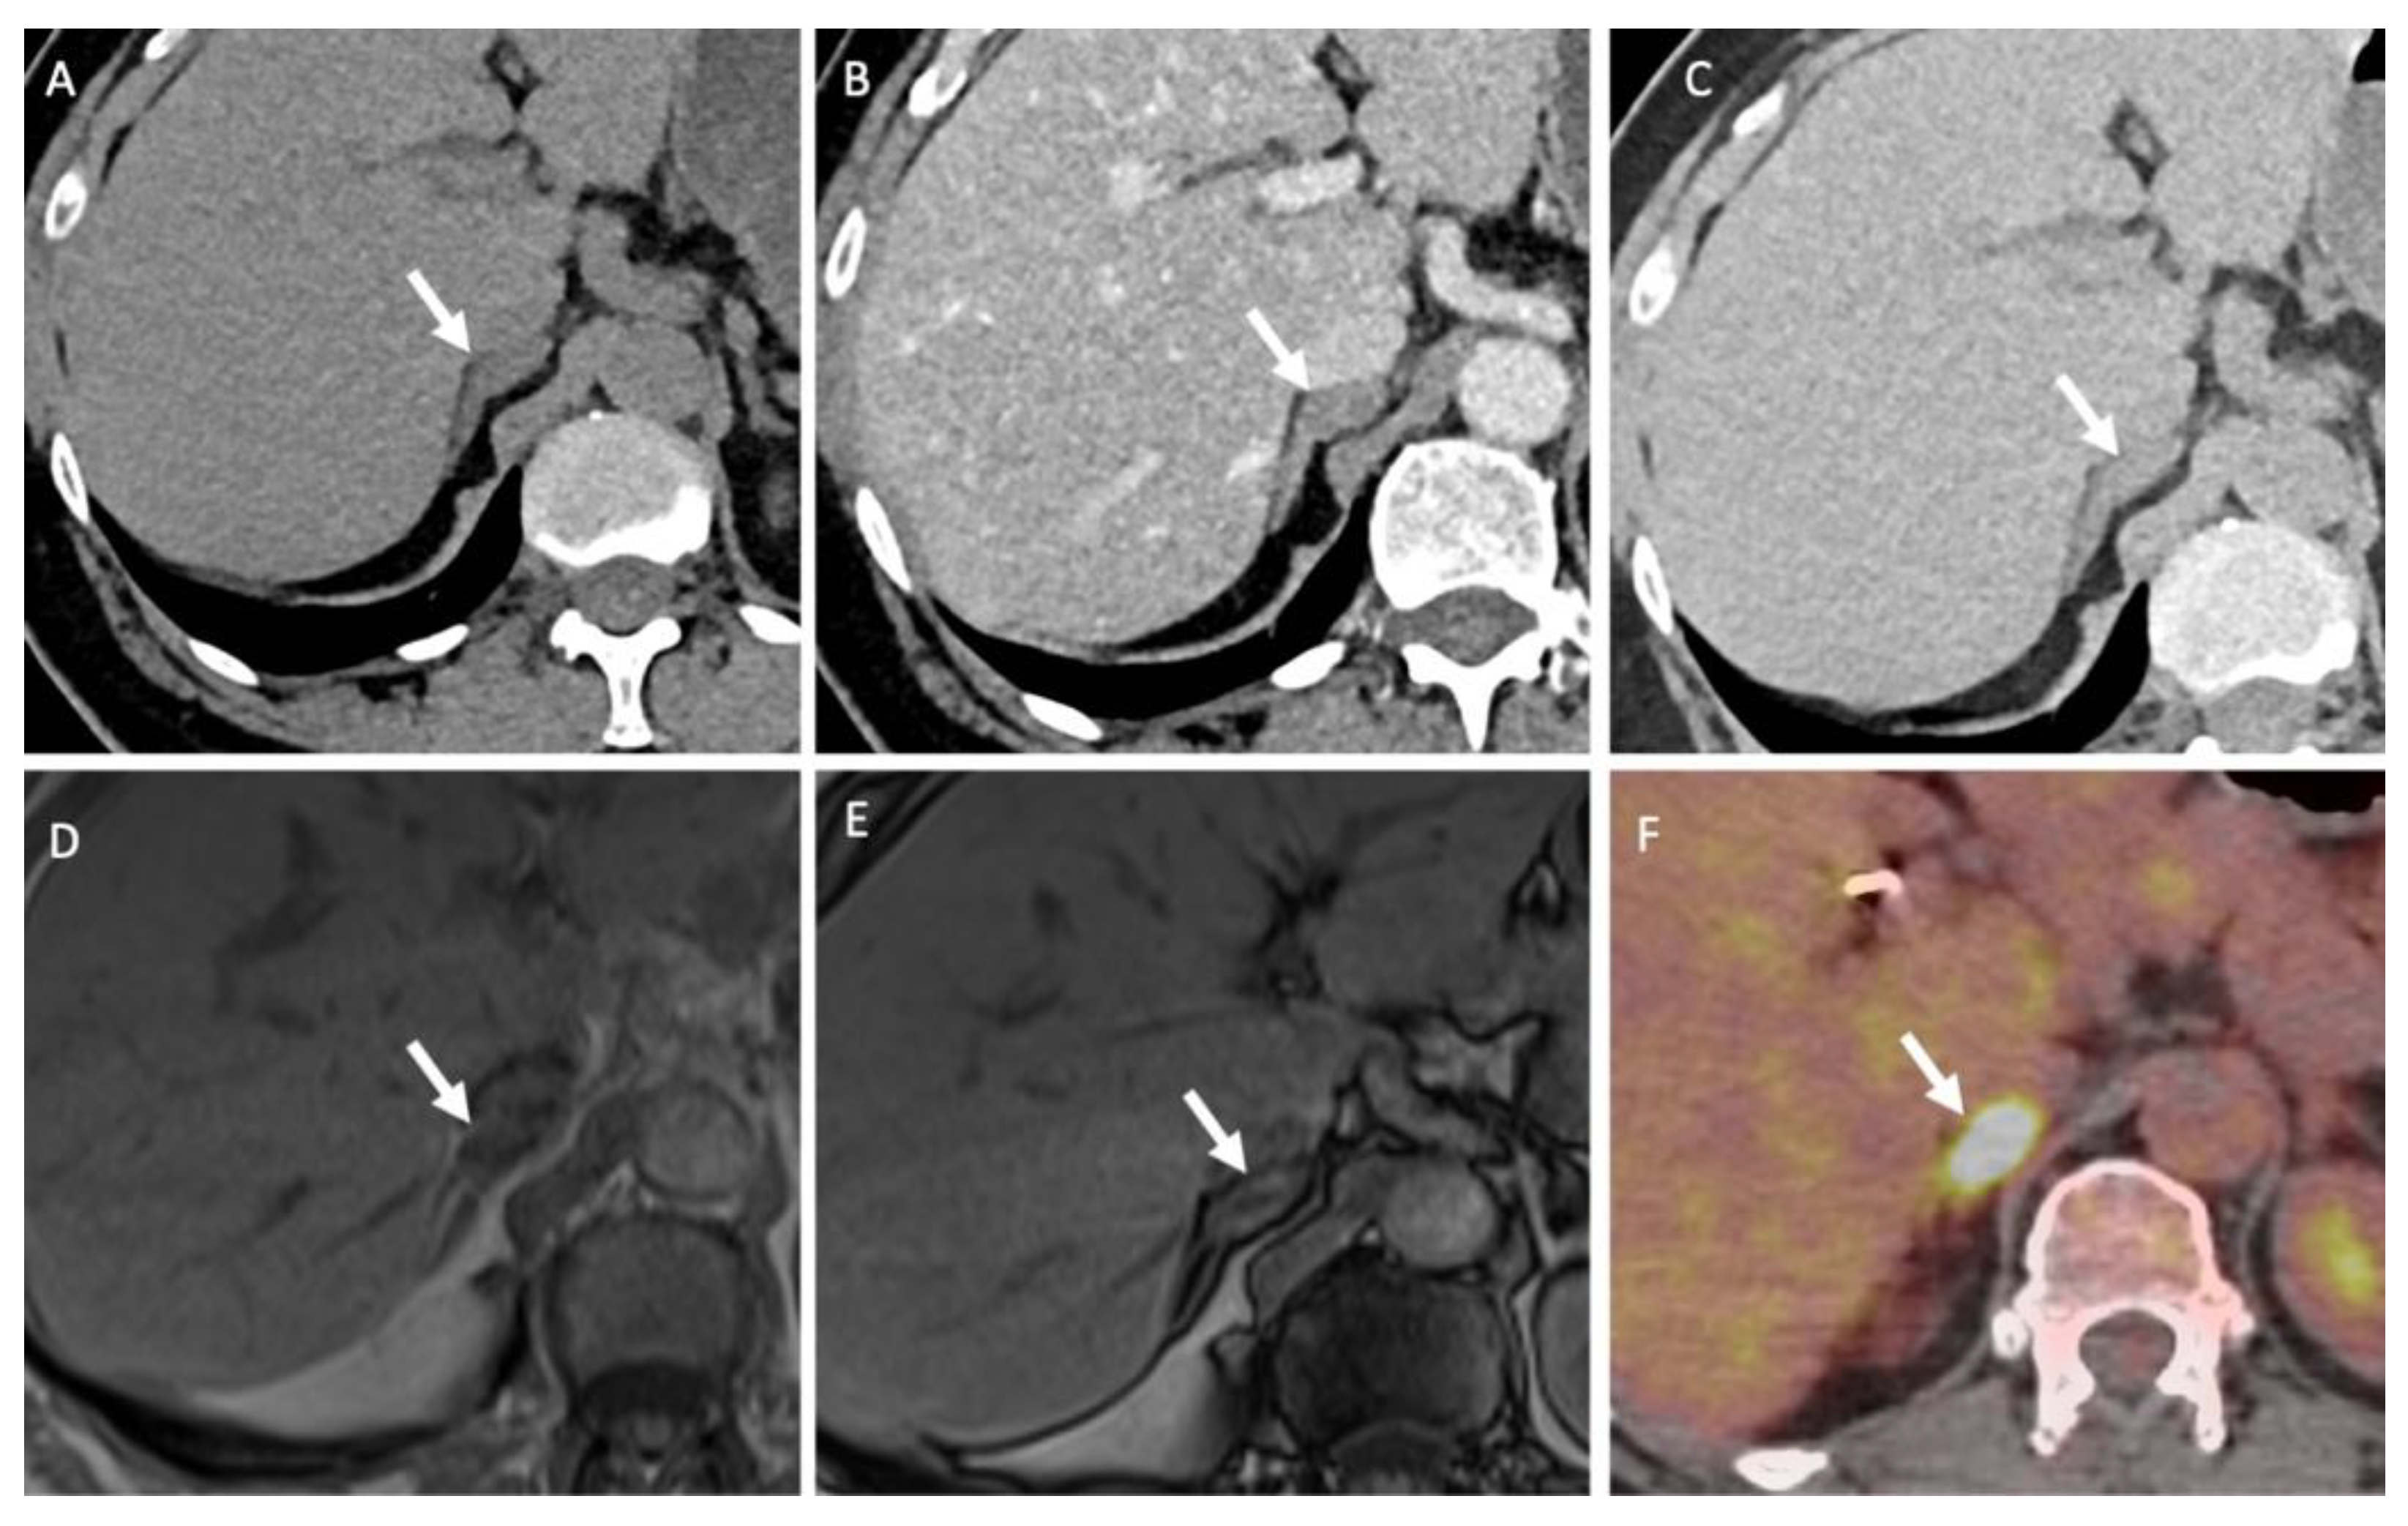

- Seo, J.M.; Park, B.K.; Park, S.Y.; Kim, C.K. Characterization of lipid-poor adrenal adenoma: Chemical-shift MRI and washout CT. Am. J. Roentgenol. 2014, 202, 1043–1050. [Google Scholar] [CrossRef]

- Haider, M.A.; Ghai, S.; Jhaveri, K.; Lockwood, G. Chemical shift MR imaging of hyperattenuating (>10 HU) adrenal masses: Does it still have a role? Radiology 2004, 231, 711–716. [Google Scholar] [CrossRef]

- Platzek, I.; Sieron, D.; Plodeck, V.; Borkowetz, A.; Laniado, M.; Hoffmann, R.T. Chemical shift imaging for evaluation of adrenal masses: A systematic review and meta-analysis. Eur. Radiol. 2019, 29, 806–817. [Google Scholar] [CrossRef]

- Stanzione, A.; Verde, F.; Galatola, R.; Romeo, V.; Liuzzi, R.; Mainenti, P.P.; Aprea, G.; Klain, M.; Guadagno, E.; Del Basso De Caro, M.; et al. Qualitative Heterogeneous Signal Drop on Chemical Shift (CS) MR Imaging: Correlative Quantitative Analysis between CS Signal Intensity Index and Contrast Washout Parameters Using T1-Weighted Sequences. Tomography 2021, 7, 961–971. [Google Scholar] [CrossRef]

- Romeo, V.; Maurea, S.; Guarino, S.; Mainenti, P.P.; Liuzzi, R.; Petretta, M.; Cozzolino, I.; Klain, M.; Brunetti, A. The role of dynamic post-contrast T1-w MRI sequence to characterize lipid-rich and lipid-poor adrenal adenomas in comparison to non-adenoma lesions: Preliminary results. Abdom. Radiol. (NY) 2018, 43, 2119–2129. [Google Scholar] [CrossRef] [PubMed]

- Miller, F.H.; Wang, Y.; McCarthy, R.J.; Yaghmai, V.; Merrick, L.; Larson, A.; Berggruen, S.; Casalino, D.D.; Nikolaidis, P. Utility of diffusion-weighted MRI in characterization of adrenal lesions. Am. J. Roentgenol. 2010, 194, W179–W185. [Google Scholar] [CrossRef] [PubMed]

- Halefoglu, A.M.; Altun, I.; Disli, C.; Ulusay, S.M.; Ozel, B.D.; Basak, M. A prospective study on the utility of diffusion-weighted and quantitative chemical-shift magnetic resonance imaging in the distinction of adrenal adenomas and metastases. J. Comput. Assist. Tomogr. 2012, 36, 367–374. [Google Scholar] [CrossRef]

- Groussin, L.; Bonardel, G.; Silvera, S.; Tissier, F.; Coste, J.; Abiven, G.; Libe, R.; Bienvenu, M.; Alberini, J.L.; Salenave, S.; et al. 18F-Fluorodeoxyglucose positron emission tomography for the diagnosis of adrenocortical tumors: A prospective study in 77 operated patients. J. Clin. Endocrinol. Metab. 2009, 94, 1713–1722. [Google Scholar] [CrossRef]

- Satoh, K.; Patel, D.; Dieckmann, W.; Nilubol, N.; Kebebew, E. Whole Body Metabolic Tumor Volume and Total Lesion Glycolysis Predict Survival in Patients with Adrenocortical Carcinoma. Ann. Surg. Oncol. 2015, 22 Suppl. 3, S714–S720. [Google Scholar] [CrossRef]

- Brady, M.J.; Thomas, J.; Wong, T.Z.; Franklin, K.M.; Ho, L.M.; Paulson, E.K. Adrenal nodules at FDG PET/CT in patients known to have or suspected of having lung cancer: A proposal for an efficient diagnostic algorithm. Radiology 2009, 250, 523–530. [Google Scholar] [CrossRef]